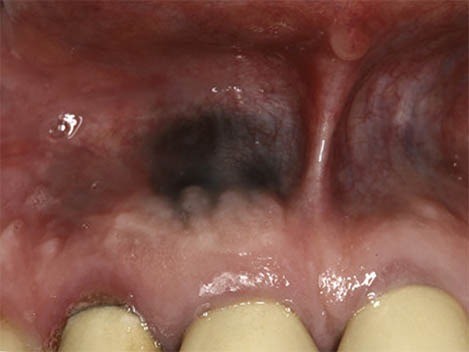

Occasionally, a swollen spot known as an eruption hematoma can form over a child’s erupting tooth. When this small, fluid-filled cyst contains blood it appears dark blue or purple. The word “hematoma” refers to an area filled with blood, just like any bruise you might get from bumping your knee or elbow. This is a harmless lesion that requires no treatment and will disappear as the tooth grows into the mouth.